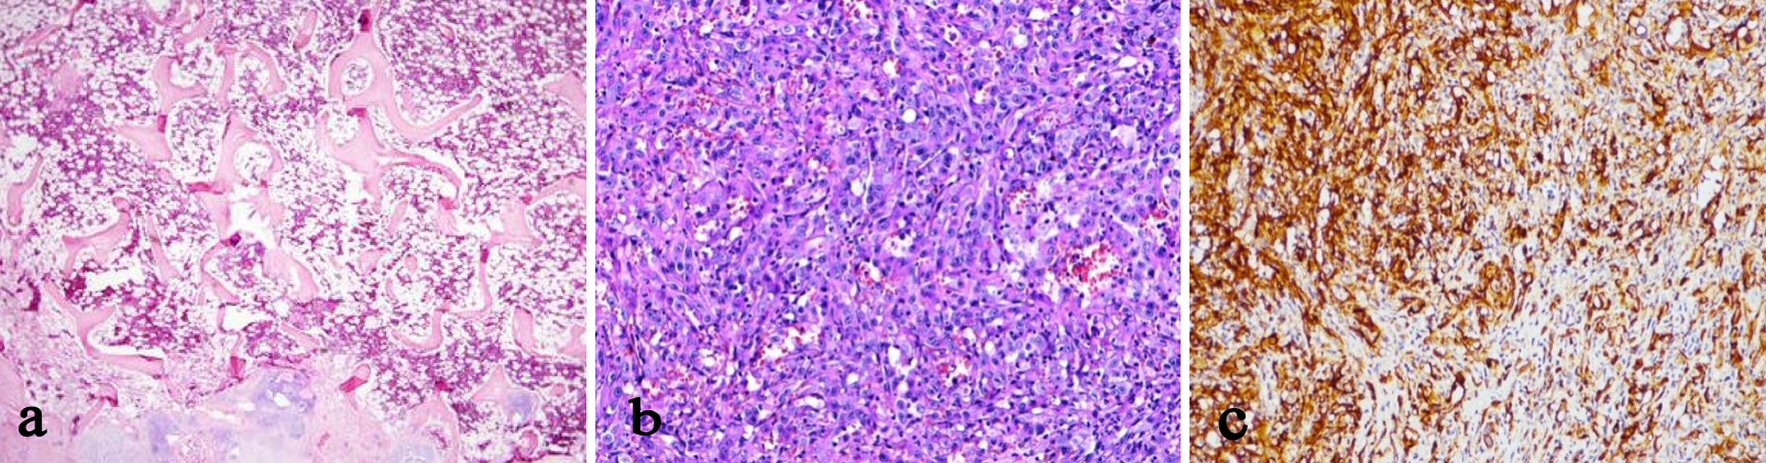

The first biopsy was not definitive in describing the sample as partially degenerated bone fragment containing low degree chronic inflammation and focal fibrochondroid tissue. The second biopsy was carried out to rule out malignancy. The second biopsy revealed osteoclastic giant cells between bone lamella and proliferated vascular tissue with epithelioid morphology containing atypical fusiform cell proliferation. The immunohistochemical analysis with CD31 stain was positive supporting the diagnosis of angiosarcoma (Fig. 3a-c).

![]() Click for large image | Figure 3. (a) Normal bone histology, × 40 magnification. (b) Hematoxylin-eosin stain. (c) Immunohistochemical stain with CD31. |

The etiology of malignant vascular bone tumors is unclear. The early diagnosis with biopsy may be the only chance of the patient to survive. The definitive diagnosis is done with histological and immunohistochemical tests [4]. The key of the immunohistochemical examination is the application of vascular markers for the diagnosis of epithelioid angiosarcoma. The most sensitive vascular marker is CD31 [5]. Factor VIII and CD34 markers are the other useful markers for diagnostic studies. Desphande et al examined 10 patients and proved 75% patients as positive with factor VIII and 40% patients as positive with CD34 markers [5]. Our patient was stained positive with the most sensitive marker, CD31.